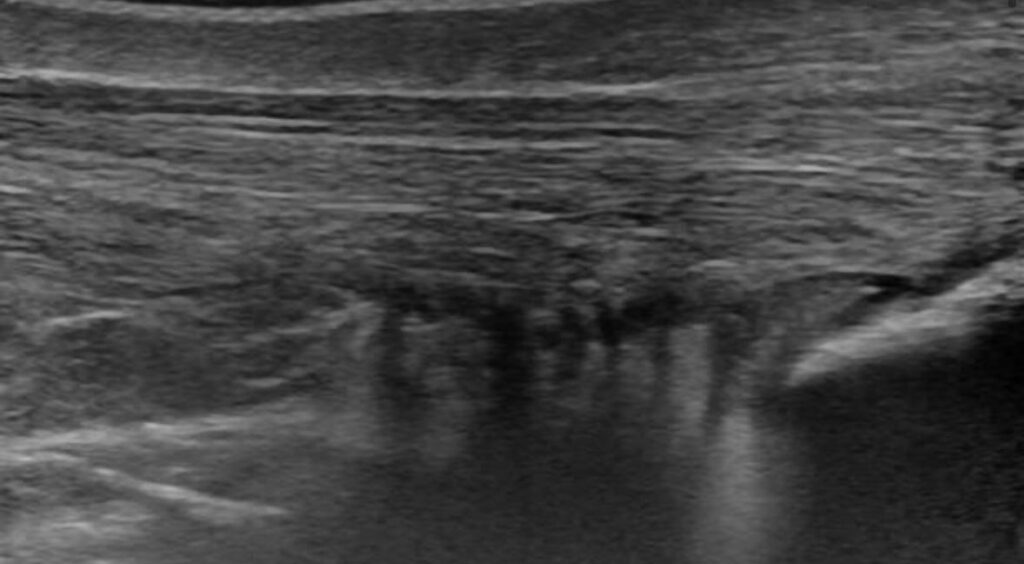

Tendinopatía del tendón de Aquiles

En esta imagen muestra un tendón de Aquiles engrosado. Mientras que la parte de la izquierda (proximal) mantiene un tamaño normal, la parte de la derecha (distal) el tendón se abomba.

Ese engrosamiento difuso es un signo típico de las tendinopatías, que en este caso el paciente sufría desde hacía 1 año. Igualmente, la imagen muestra neovascularización asociada a la tendinopatía del tendón de Aquiles.